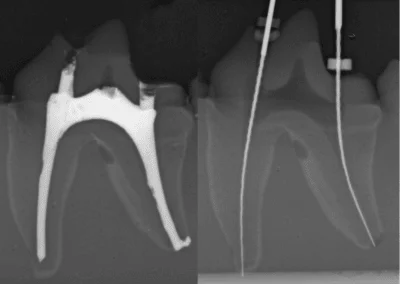

Train radiographic positioning without interruptions. GAIA allows you to follow the procedure just like in a real case, without repositioning cadavers for every scan.

| X-ray Compatible | ✅ Yes | ❌ No | ✅ Yes | ❌ No |